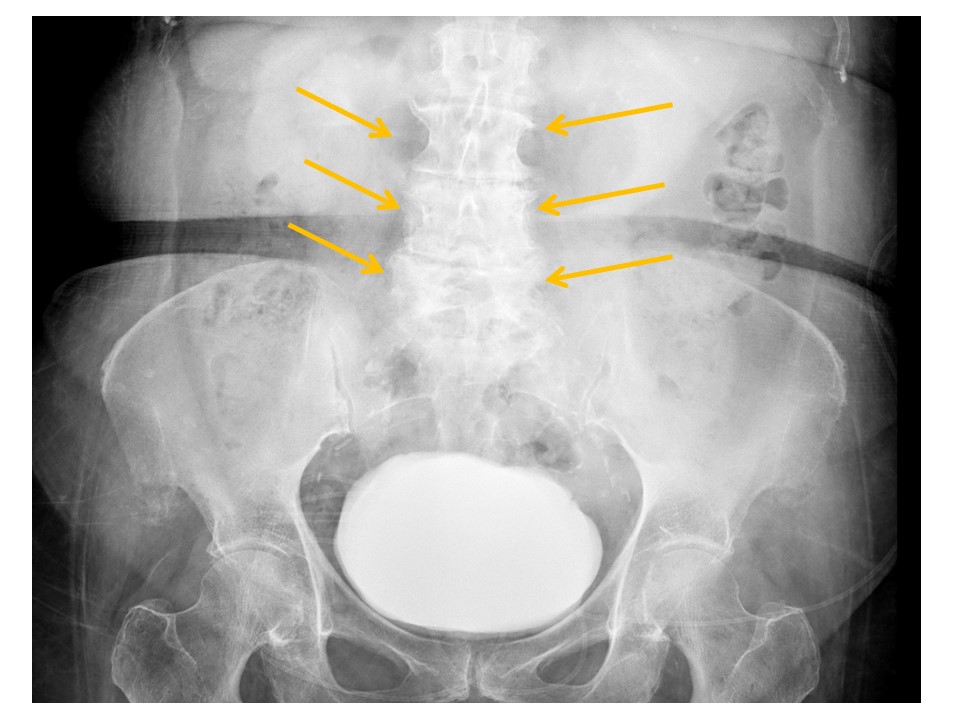

VISUALIZED LUMBAR SPINE

There are compression fractures. [Yes/No]

There are transverse process fractures. [Yes/No]

SACRUM and SACROILIAC JOINTS

There are displaced fractures or disrupted/asymmetric foraminal arcs. [Yes/No]

The sacroiliac joints are widened and asymmetric. [Yes/No]

There is malalignment at the inferior margin of the sacroiliac joints. [Yes/No]